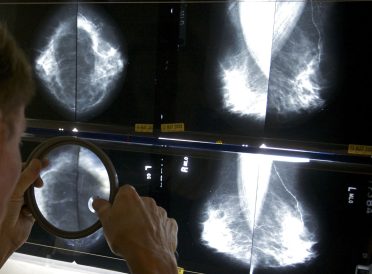

article image -

A Canadian study many experts said has major flaws has revived debate about the value of mammograms. The research suggests these screening X-rays do not lower the risk of dying of breast cancer while finding many tumors do not need treatment.

The study gives longer follow-up on nearly 90,000 women who had annual breast exams by a nurse to check for lumps plus a mammogram, or the nurse’s breast exam alone. After more than two decades, breast cancer death rates were similar in the two groups, suggesting little benefit from mammograms.

Critics of the Canadian study also said it used outdated equipment and poor methods that made mammograms look unfairly ineffective.